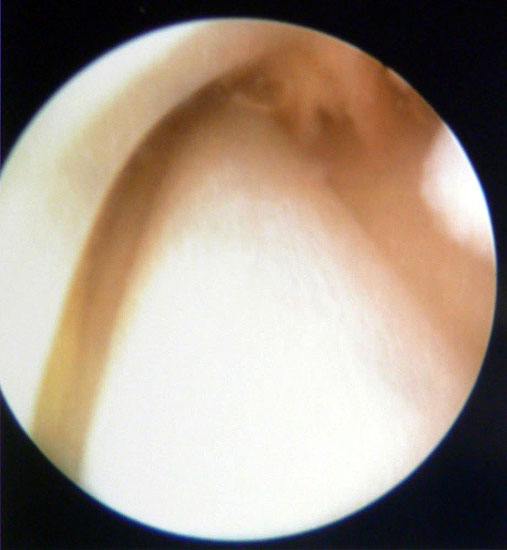

Tendoskopie

Tendoskopie der Peronealsehnen. Aufgrund der engen Raumverhältnisse sind die therapeutischen Möglichkeiten limitiert.

Abbildung 7

Die Tendoskopie bietet eine weitere Möglichkeit Sehnenpathologien zu visualisieren. Dieses invasive diagnostische Verfahren hat angesichts der immer höher werdenden MRT-Auflösung und den Möglichkeiten der dynamischen Untersuchung mit hochfrequenten Ultraschallköpfen keine größere Verbreitung erfahren. Die therapeutischen Möglichkeiten des Verfahrens beschränken sich auf eine lokale Synovektomie, die Lösung von Verklebungen und dem Abtragen von Knochenkanten 13141516.